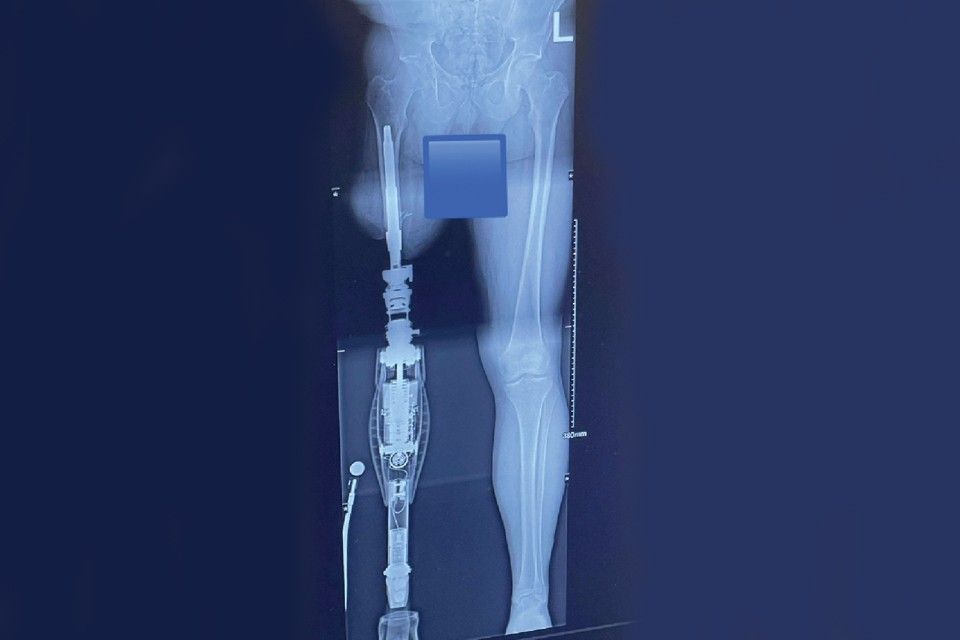

Osseointegration is now an advanced reconstructive surgery technique for amputees. The implant connects directly with the bone of the residual limb for the purpose of better body awareness and superior balance and gait.

The procedure inserts a titanium implant into the marrow space of the bone. The rod becomes integrated over time to become part of the bone. The other end of the implant extends through the soft tissue for direct attachment to the prosthetic device.

Osseointegration is said to offer recipients improved function and mobility without pinching, sweating, muscle weakness and skin irritation. Osseo bone-anchored prostheses can be implanted in the humerus (upper arm bone), radius or ulna (forearm bones), femur (thigh bone), or tibia (lower leg bone).